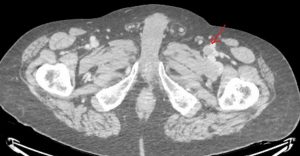

CT and MRI can also diagnose deep vein thrombosis. They are most useful for identifying findings in the abdomen and pelvis. However, they are sometimes used to assess the veins in the extremities, like in this example: